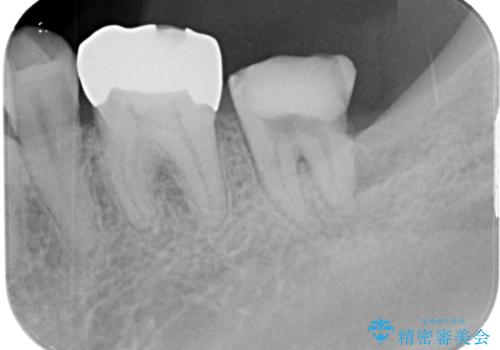

診査の結果、下顎左側第二大臼歯の遠心(奥側)に大きな虫歯があり、歯肉の奥深く、骨の縁まで進行している状態でした。

このようなケースでは、虫歯を完全に除去して精密な補綴治療をするのが難しく、長期的な予後が不良となることが多いです。

そこで今回は、抜歯即時インプラントの適応と判断しました。